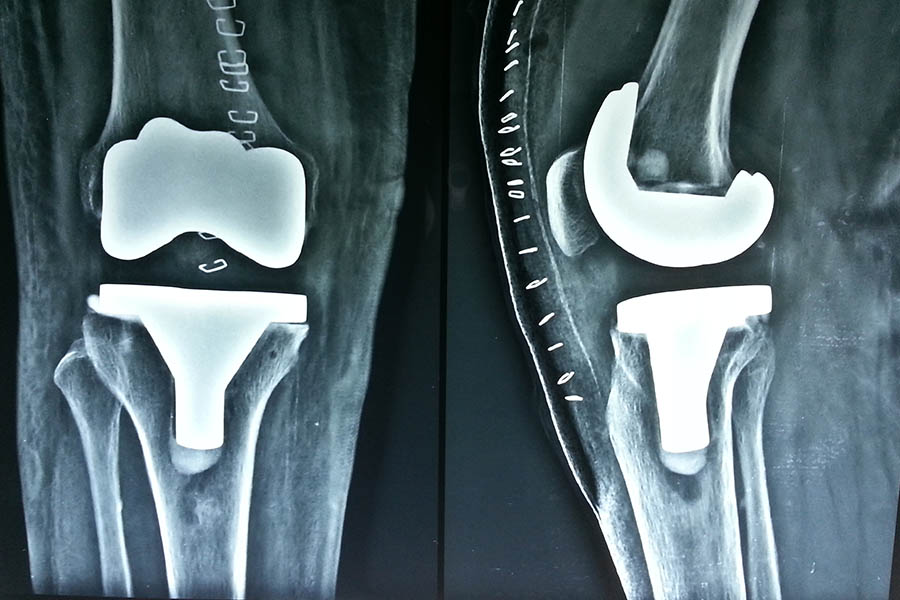

Total Knee Replacement

Case 1